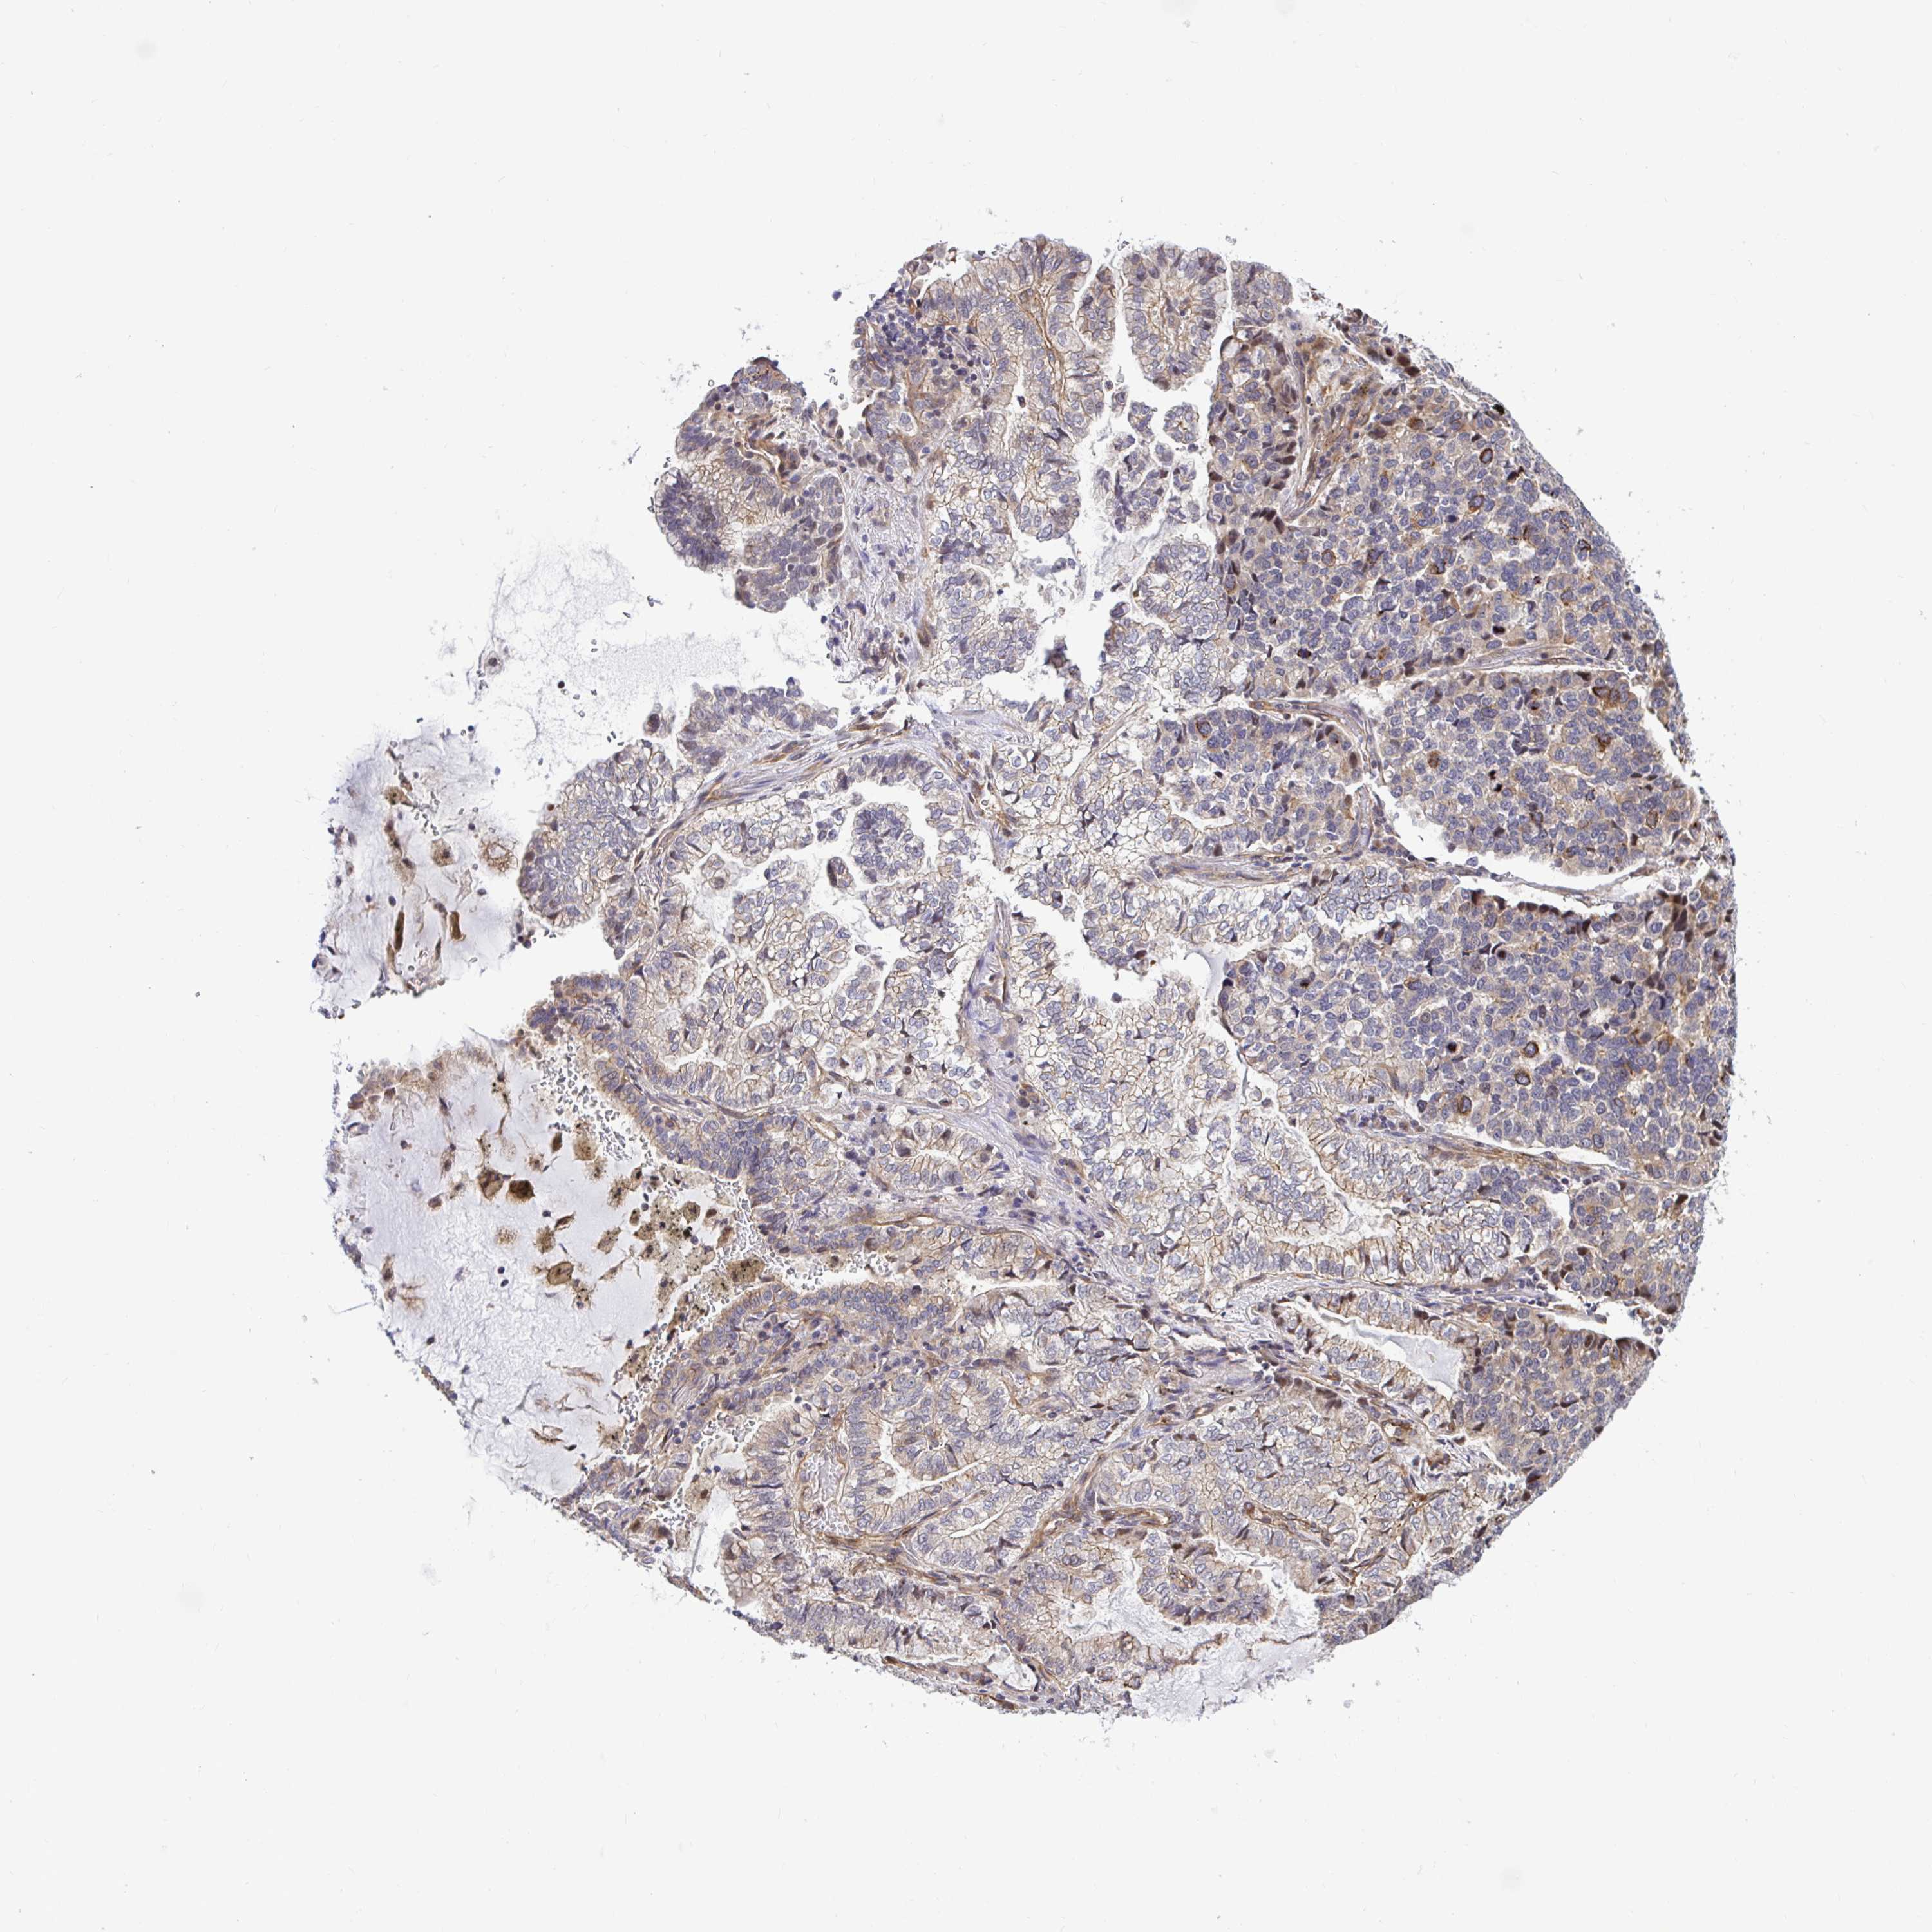

LUNG ADENOCARCINOMA (VALIDATION) - Interactive survival scatter ploti

The Survival Scatter plot shows the clinical status (i.e. dead or alive) for all individuals in the patient cohort, based on the same data that underlies the corresponding Kaplan-Meier plots. Patients that are alive at last time for follow-up are shown in blue and patients who have died during the study are shown in red.

The x-axis shows the expression levels (FPKM) of the investigated gene in the tumor tissue at the time of diagnosis. The y-axis shows the follow-up time after diagnosis (years). Both axes are complimented with kernel density curves demonstrating the data density over the axes. The top density plot shows the expression levels (FPKM) distribution among dead (red) and alive patients (blue). The right density plot shows the data density of the survived years of dead patients with high and low expression levels respectively, stratified using the cutoff indicated by the vertical dashed line through the Survival Scatter plot. This cutoff is automatically defined based on the FPKM cutoff that minimizes the p-score. The cutoff can be changed by dragging the vertical line or by entering a cutoff value in the square labeled "Current cut-off".

Under the Survival Scatter plot the p-score landscape (black curve; left axis) is shown together with dead median separation (red curve; right axis). Dead median separation is the difference in median mRNA expression between patients who have died with high and low expression, respectively. It is calculated as follows: median FPKM expression of dead patients with high expression - median FPKM expression of dead patients with low expression. This is intended to aid the user in visually exploring custom cutoffs and the associated p-scores and dead median separation.

Individual patient data is displayed and can be filtered by clicking on one or more of the category buttons on the top of the page. Categories describing expression level and patient information include: high, low, alive, dead, female, male and tumor stages. The scale of the x-axis can be toggled between linear and log-scale by clicking on the "x log" button. Mouse-over function shows TCGA ID, patient information and mRNA expression (FPKM) for each patient.

& Survival analysisi

Kaplan-Meier plots summarize results from analysis of correlation between mRNA expression level and patient survival. Patients were divided based on level of expression into one of the two groups "low" (under cut off) or "high" (over cut off). X-axis shows time for survival (years) and y-axis shows the probability of survival, where 1.0 corresponds to 100 percent.

TRIM55 is not prognostic in Lung Adenocarcinoma (validation)